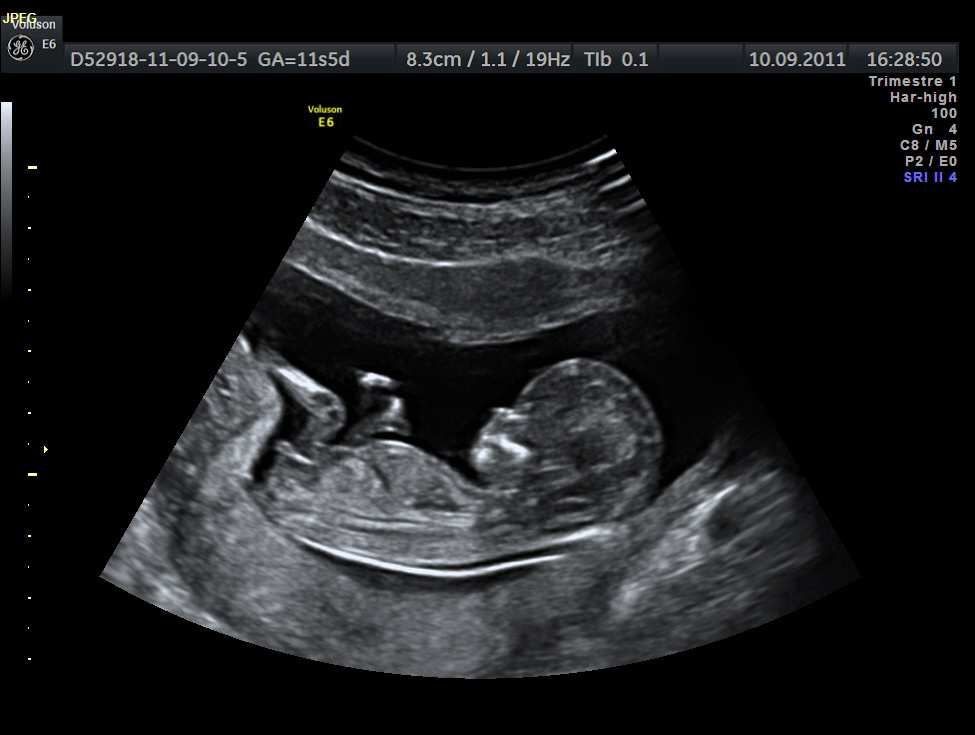

4D Scan لمتابعة جنينك أول بأول

عيشي تجربة مميزة مع تقني ة فور دي سكان وتفاصيله بدقة عالية، والاطمئنان على نموه في كل مرحلة من مراحل الحمل.فحص آمن،

صورة أوضح، ومتابعة لحظية تحت إشراف طبي متخصص لأن راحة بالك تهمنا

تابعي جنينك لحظة بلحظة مع ، دقة عالية، صور واضحة، واطمئنان مستمر على صحة الجنين بإشراف طبي.